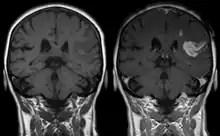

Les chélates de Gd3+ sont hydrophiles et franchissent seulement une barrière hémato-encéphalique compromise, telle que les lésions et les tumeurs.

Le gadolinium (sous forme chélatée ou libre) est retenu dans le cerveau, en particulier dans le noyau dentelé et le globus pallidus[11], dès une injection d'un agent de contraste à base de gadolinium (GBCA) (en quantité plus importante pour les linéaires)[12]. Le système glymphatique pourrait être la voie d'accès principale des GBCA au cerveau en intraveineuse[13]. Des études in vitro ont trouvé les agents linéaires (chélateurs moins stables) plus neurotoxiques que ceux macrocycliques[14],[15]. Une étude a trouvé qu'un rehaussement du signal T1 sans administration de contraste (indicateur de la présence de gadolinium) sur les IRM cérébraux d'individus ayant reçu une ou plusieurs injections d'agents linéaires et macrocycliques corrélaient significativement avec une fluence verbale moindre[16]. La confusion est une possible conséquence clinique reportée par plusieurs études[14].